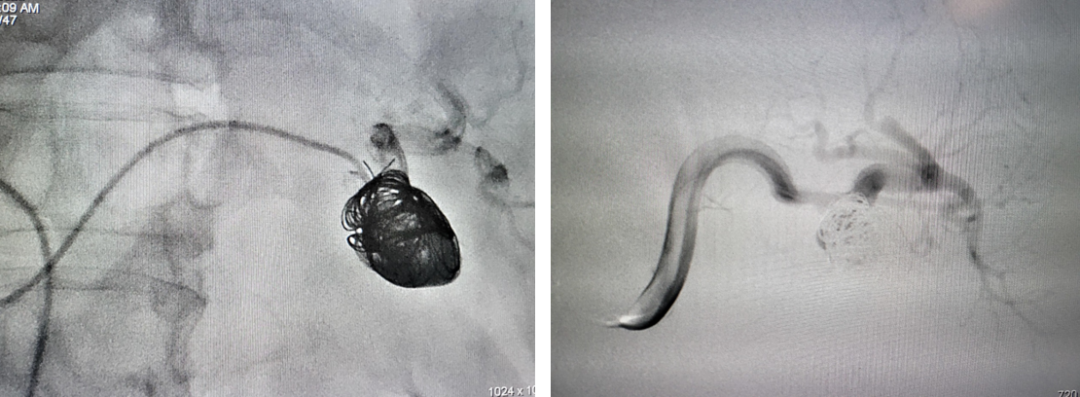

病例4 两端栓塞+瘤腔填塞

5

病例5 多发动脉瘤分支+主干栓塞

图为:分支栓塞

图为:主干栓塞最后造影